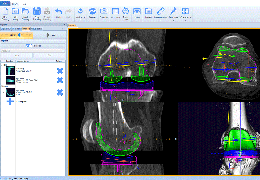

Statistical Analysis

BrainVoyager performs a wide range of statistical analyses including; parametrical mapping, contribution maps, Independent Component Analysis (ICA), Region-of-interest analysis and Event-related fMRI analysis. specifications.

Visualization Tools

Parametric and non-parametric statistical maps may be superimposed both on the original functional scans as well as onto T1-weighted 2D or 3D anatomical reference scans. Time courses of selected regions-of-interest (ROIs) are available both in 2D and 3D representations. Statistical maps may be computed either in the 2D or 3D representation since structural as well as functional 4D data (space x time) are transformed into Talairach space. This allows you to compare activated brain regions across different experiments and across different subjects